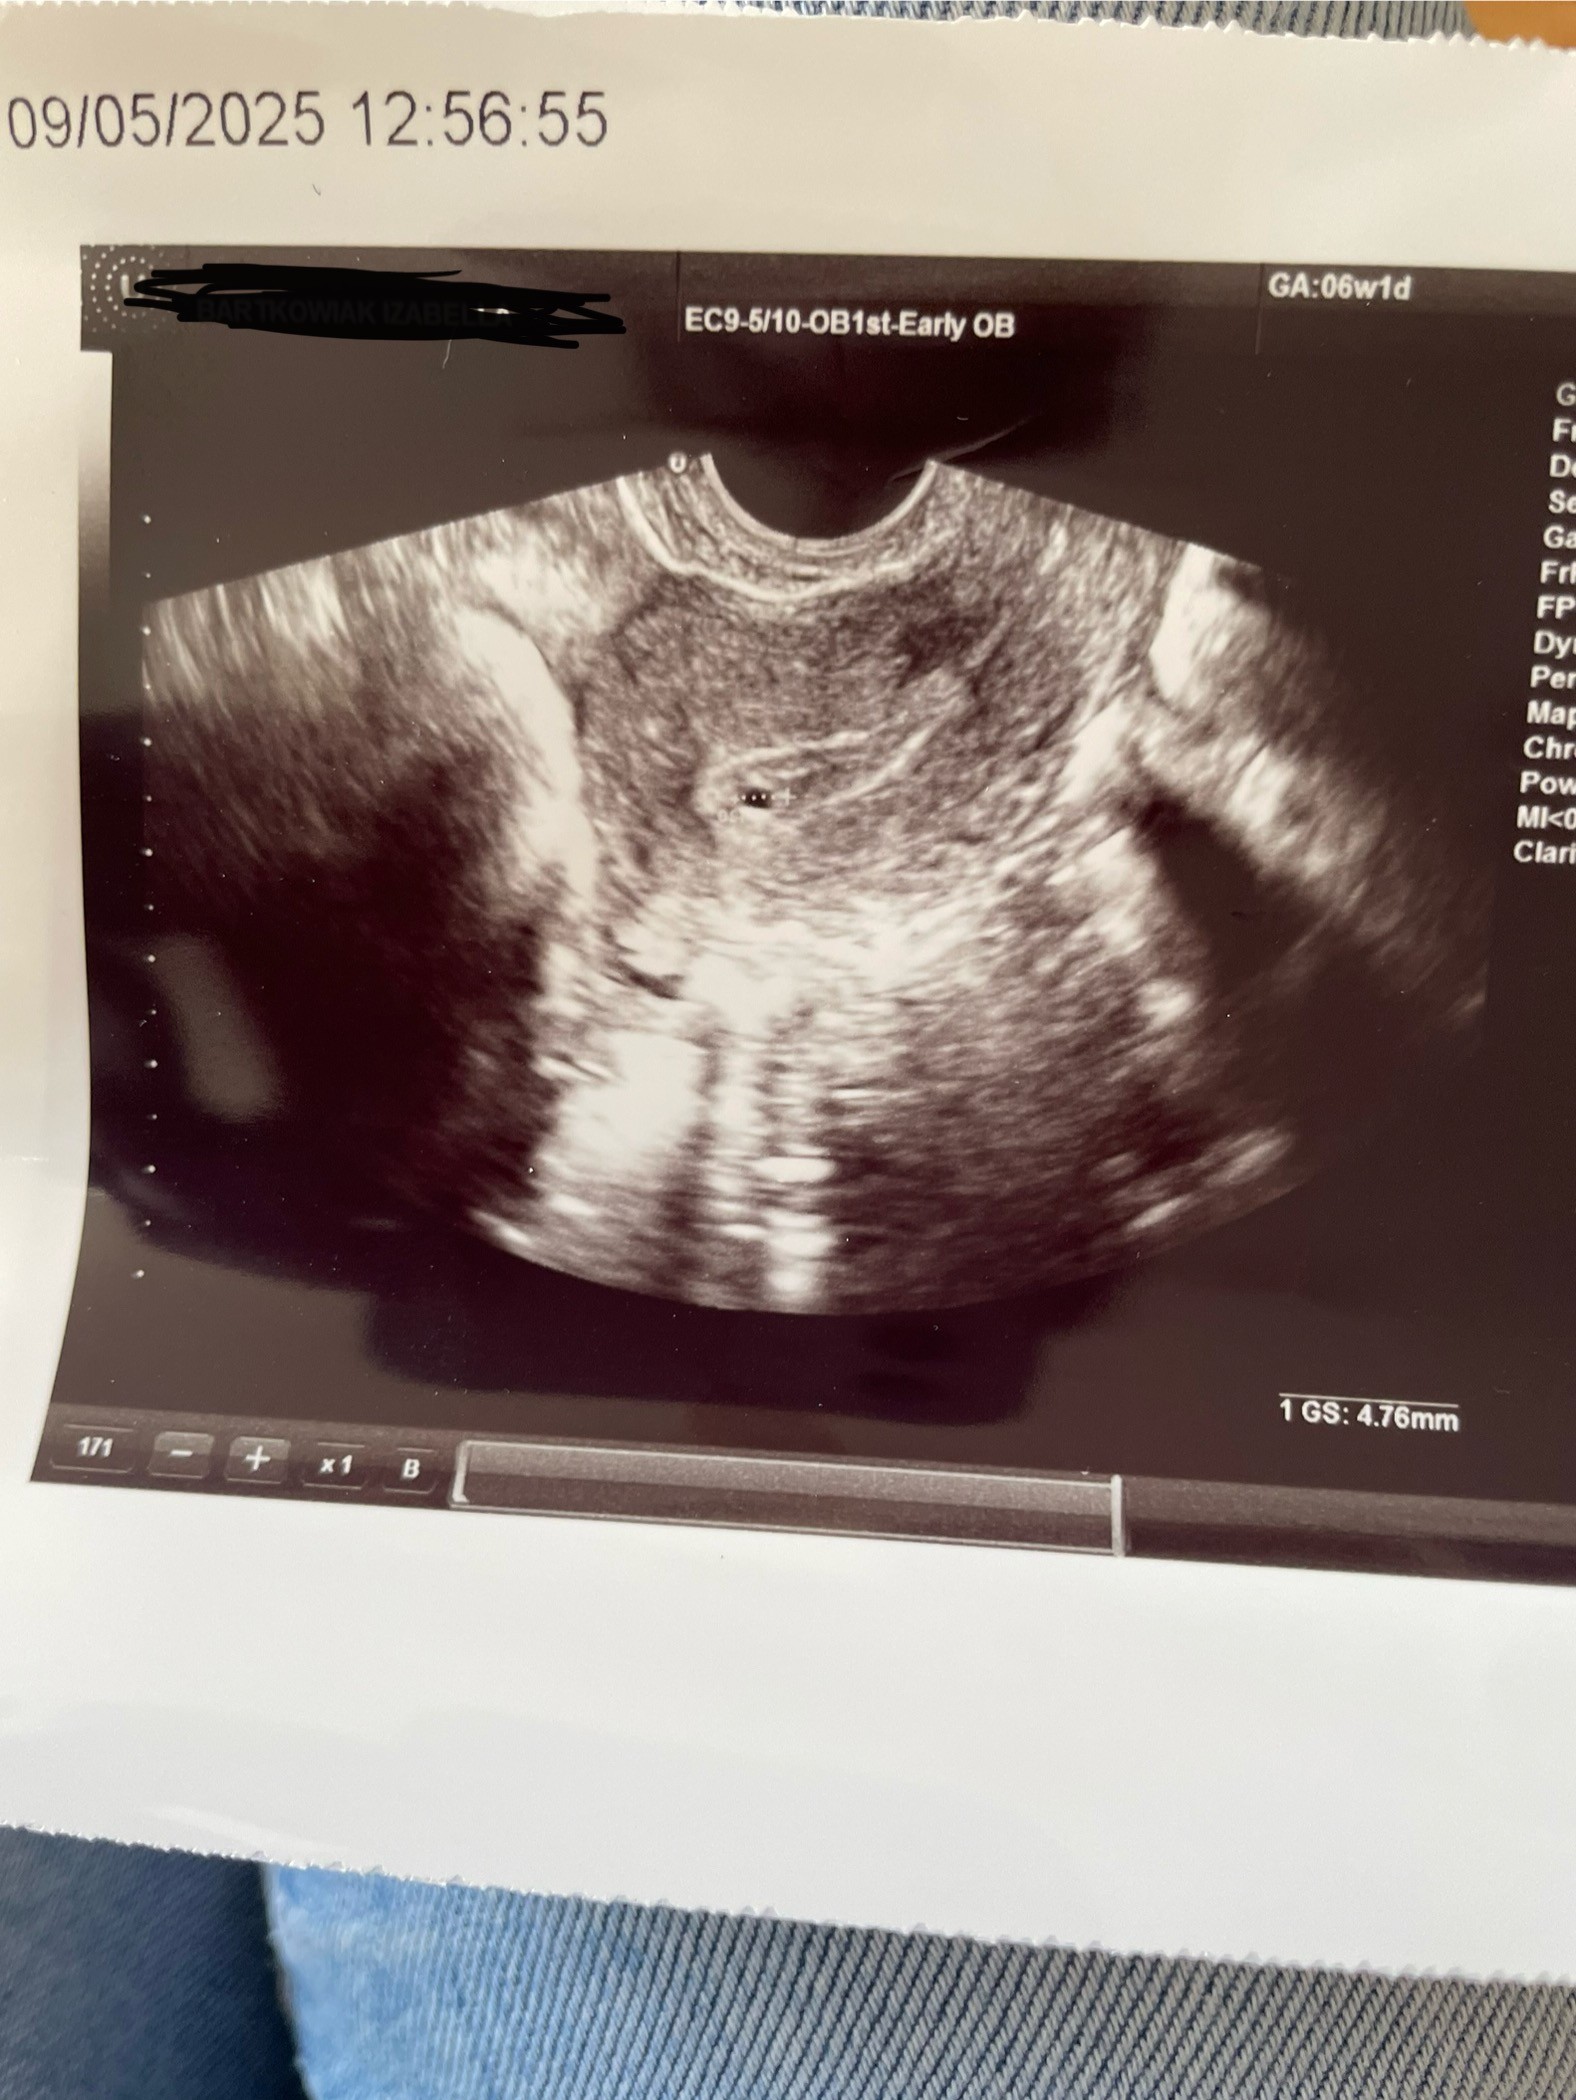

Pusty pęcherzyk

A robiłaś po drodze jakieś badania? Bete? Masz moze wymiary gdzieś na opisie z wizyty? Bo tak to cięzko gdybać.

Niestety nie robiłam żadnych innych badań po drodze lekarz powiedział że albo ciąża się rozwinie albo dojdzie do samoistnego poronienia. Jutro będę wiedziała co i jak już na 100%

IMG_0946.jpeg